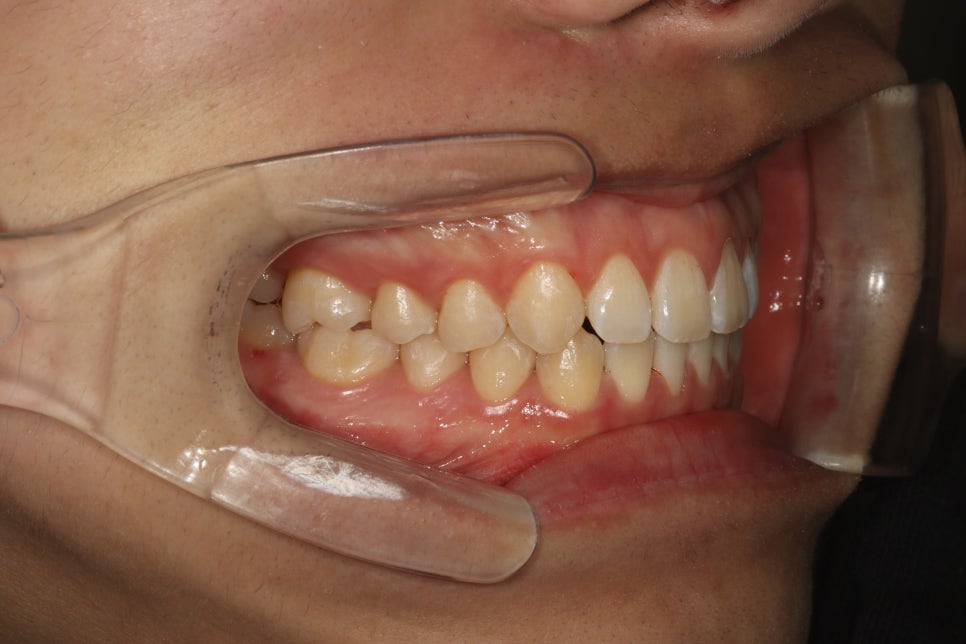

치아가 벌어져 오신 분입니다.

약 한달 정도 치료가 진행된 모습입니다.

인비절라인 장치를 보면 번호가 써 있습니다.

위 사진도 확대해서 어금니쪽을 보면 05 라고 써있죠

다섯번째 장치라는 표시입니다